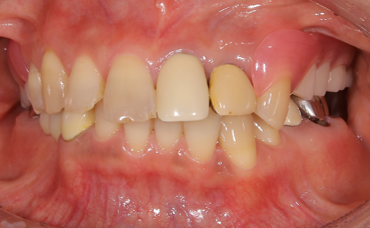

主訴:噛み心地は気にならないが話しづらさが気になる話しやすい義歯を作りたい。

元々の義歯は緑線のように前歯の裏を通るように馬蹄型に設計されており、適合性や嚙み心地は問題なかったそうですが話しづらいのが気になっていたとのことでした。

義歯は上顎の真ん中に薄い金属を通すことで話ずらさを改善しました。金属をたくさん使用していますが歯に引っかかる針金は歯茎の形をしているため見た目は義歯を装着しているようには見えません。適合性もばっちりとれています。